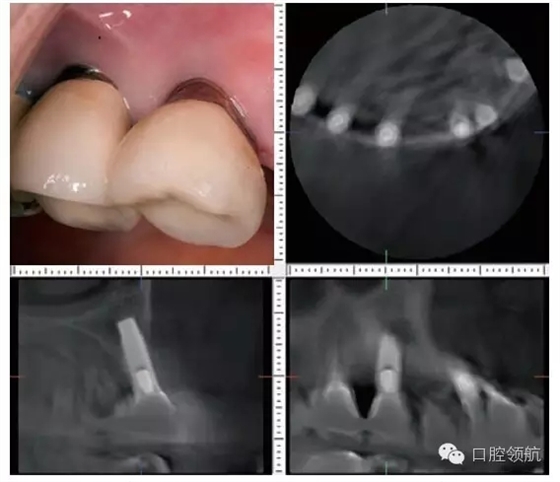

患者,66歲,女性。(左上第3顆牙)缺失的病例(圖1)(左上第4、5顆牙)部位已經(jīng)進(jìn)行了種植體修復(fù),從CBCT的影像診斷,(左上第4顆牙) 種植體頰側(cè)的骨吸收明顯,而且伴有周圍的軟組織的萎縮和種植體頸部的金屬暴露(圖2)。為了在(左上第三顆牙) 種植術(shù)后不再發(fā)生同樣的問題,有必要進(jìn)行怎樣的處理呢?

圖2 (左上第4、5顆牙) 部位口腔內(nèi)頰側(cè)面觀(右上)和(左上第4顆牙)部位的CBCT各斷層影像,植入的位置偏頰側(cè)植入方向偏頰側(cè)傾斜,因此成為種植體頰側(cè)骨板的吸收原因,(左上第4、5顆牙) 種植體頸部的金屬暴露出來。